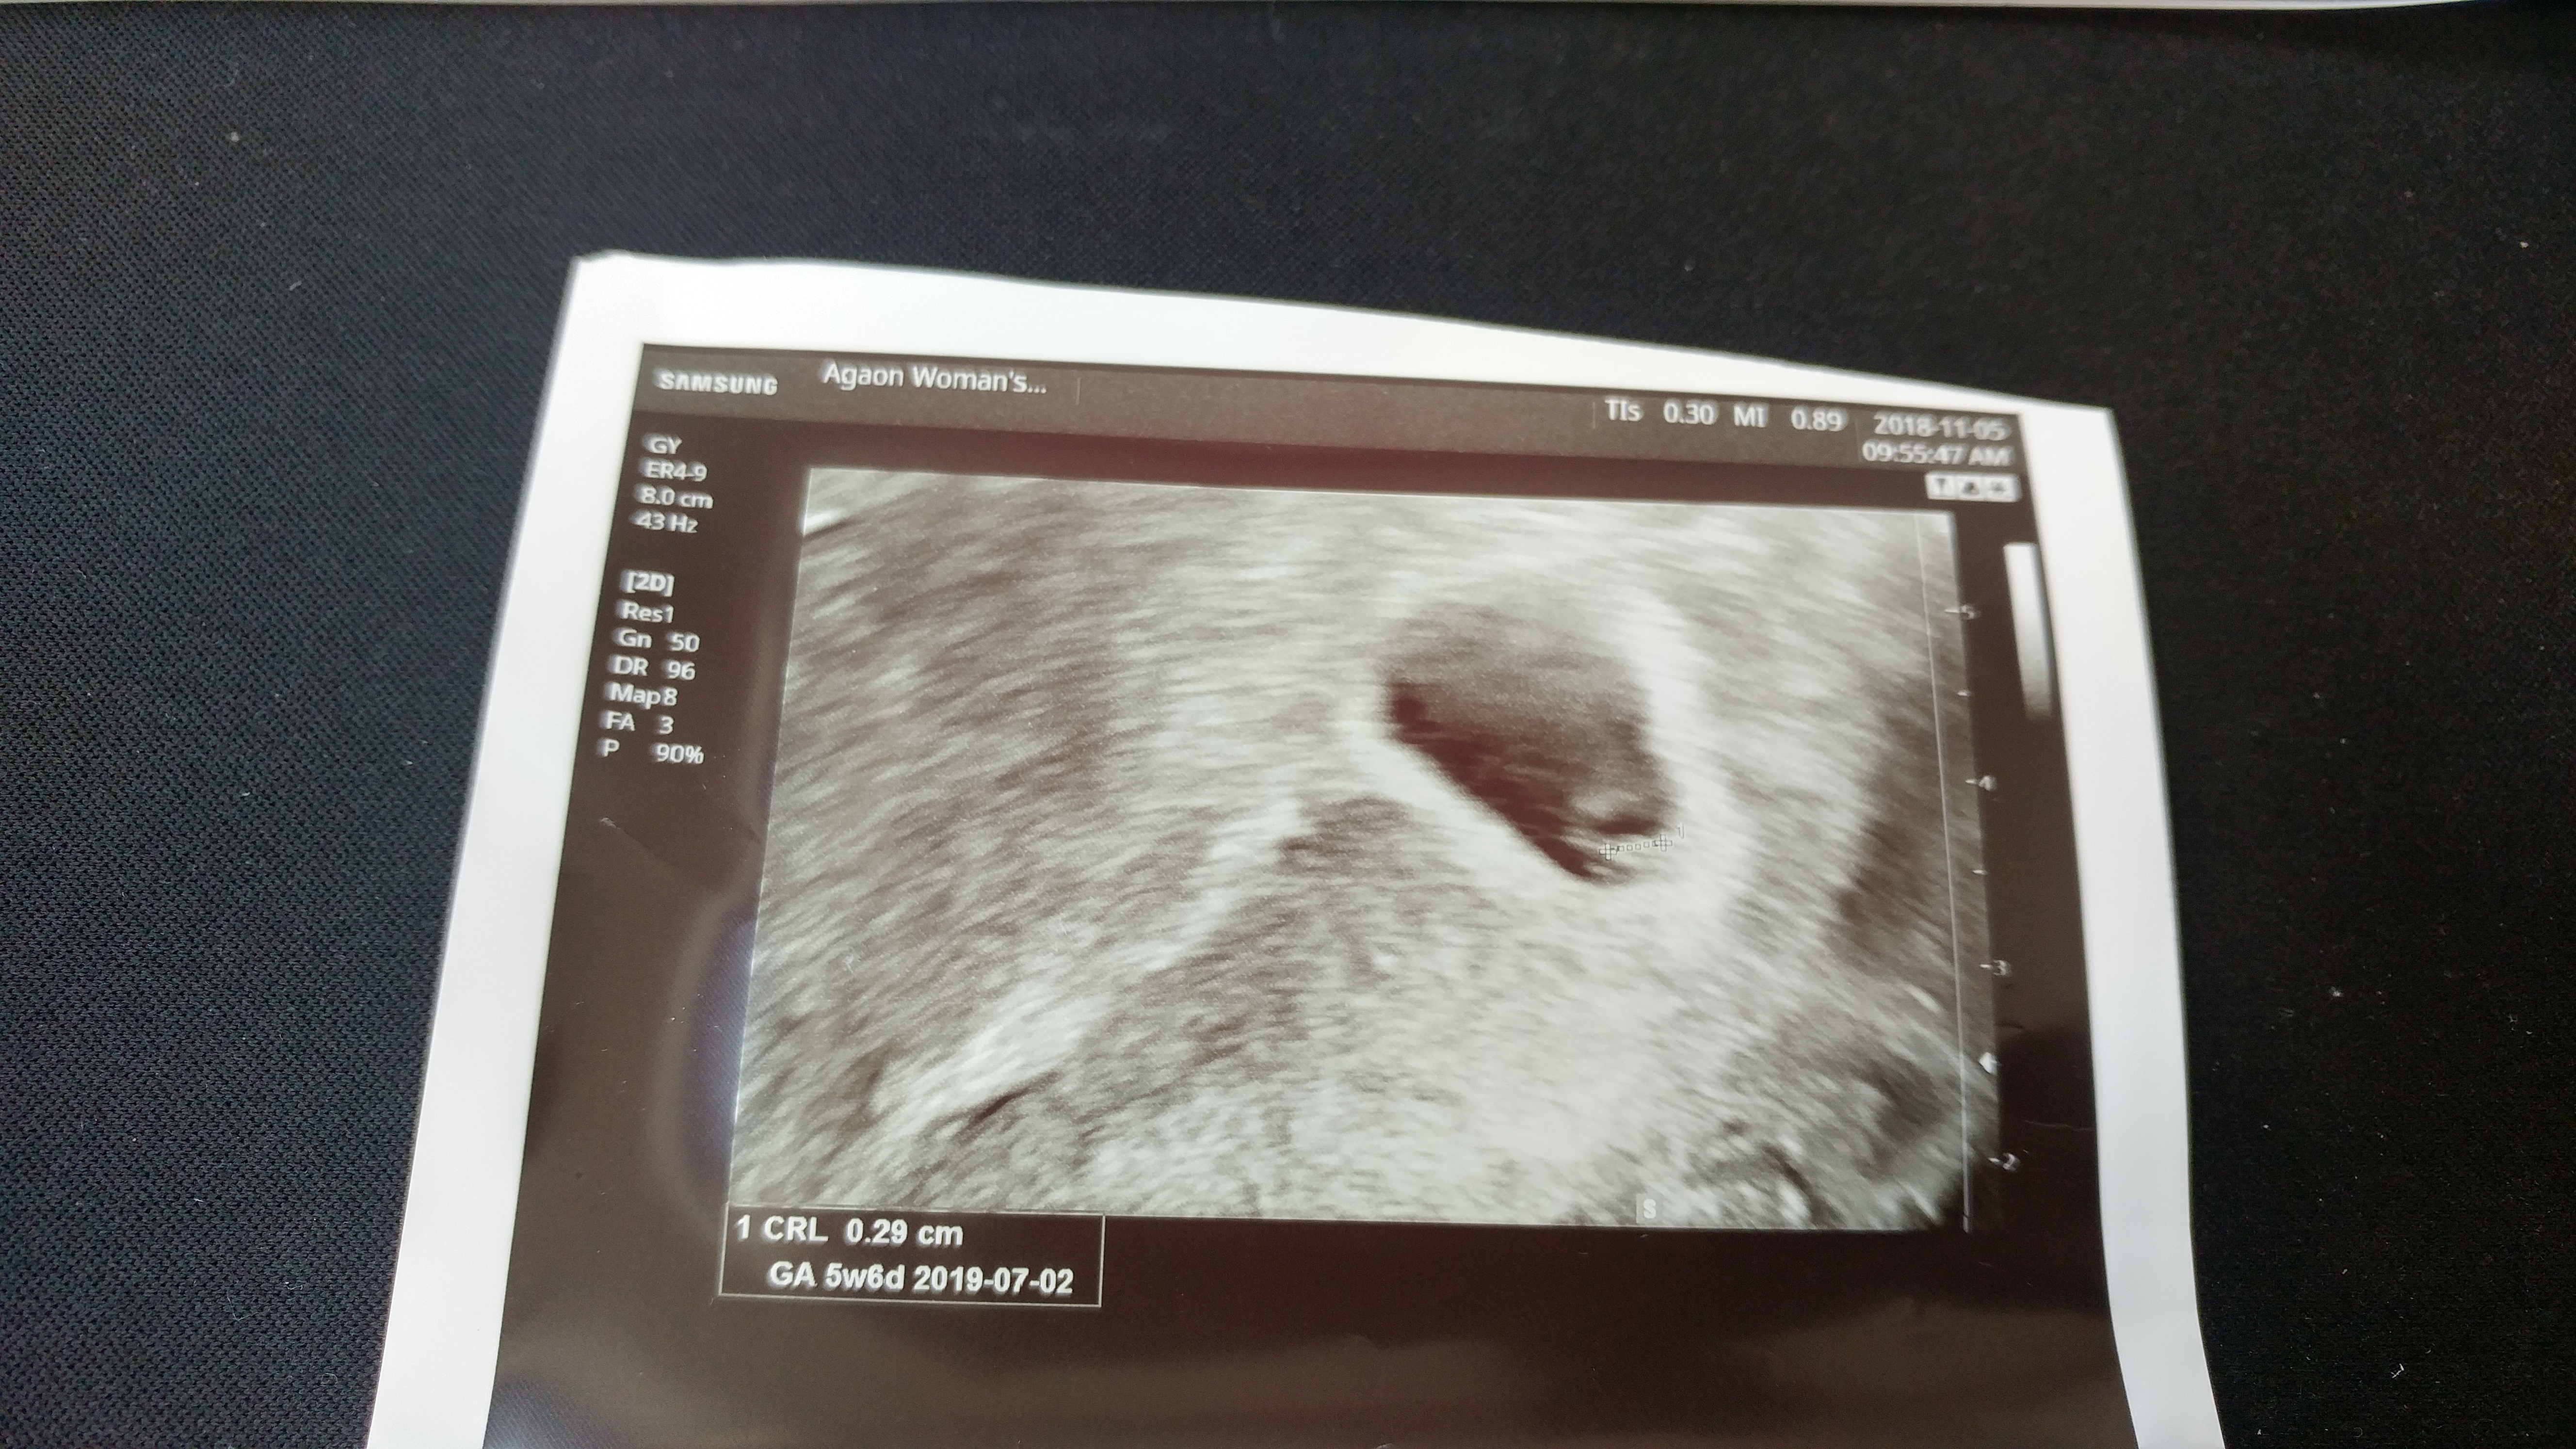

열 달 동안 포근한 경욱 엄마 뱃속에서 편안하게 잘 있어 준 내 손자 튼튼아,